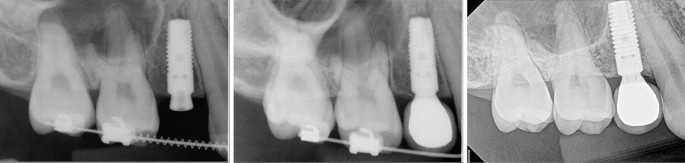

The subjects were patients who received implants at the Seoul National University Bundang Hospital, Section of Dentistry between October 2002 and September 2013. Digital panoramic radiographs of the subjects were taken at the time of oral examination, healing abutment/cover screw connection after surgery, and after loading serially. Digital periapical radiographs were also taken after surgery, at the time of superstructure connection, and at the periodic recall check-up. Radiographs were collected using a picture archiving and communication system (PACS) (INFINIT; Infinit, Seoul, Korea). Among patients, who had the implants that either injured the adjacent natural teeth or were placed with a distance of less than 1 mm from the adjacent root were selected for analysis. Patients with a follow-up record of at least one year's interval were finally included in the study.

Radiographs were taken by a single radiologic technologist, using the paralleling technique. In order to avoid false positive results due to angulation errors, the extent of implant-root contact was carefully checked by varying the x-ray taking angle when injury was noticed after surgery and during regular periodic check-ups. Tooth injury was confirmed by an oral and maxillofacial radiologist. Groups were classified according to the periapical view of the root region of the injured natural teeth: direct invasion of the root (group I), root surface contact (group II), and less than 1 mm distance of the implant from the root (group III). Considering a constant distance between the threads (thread pitch) of 0.6 mm to 0.9 mm, according to the system, the distance from the root surface to the implant was measured and calculated by the enlargement ratio in periapical radiographs.

Among the natural teeth that were injured, five of 32 teeth had already undergone root canal treatment (RCT) prior to implant placement. Five of these non-vital teeth functioned well without unusual changes, regardless of the extent of invasion (Fig. 1, Table 3). Of the 27 non-treated teeth, seven had a new RCT after implant injury due to the presentation of clinical symptoms and/or signs. Three of the seven new RCT teeth were subsequently extracted after 39 months, 7 years, and 14 years of function, respectively. One of the seven new RCT teeth was intentionally replanted after endodontic treatment and external root resorption was observed later. Although apical radiolucency was found before surgery, one of the 27 teeth was maintained without symptoms. Subsequently, 19 of 27 teeth (70.4%) remained vital and had no abnormal response during follow-up.